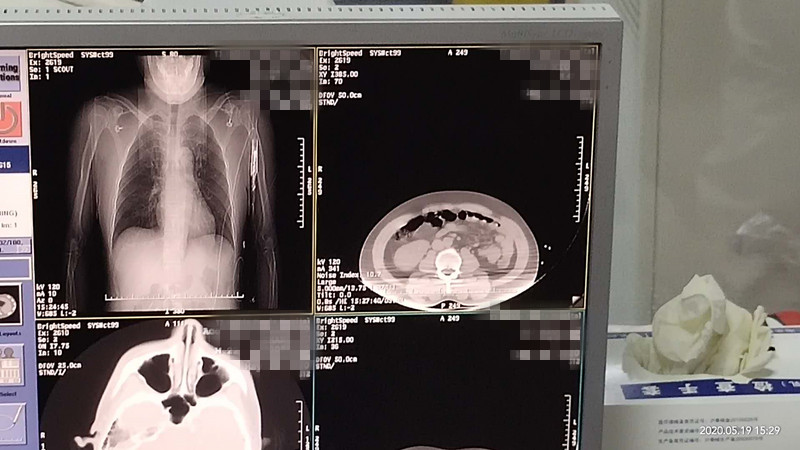

47岁腹腔氩氦刀冷冻消融

发布人:美国氩氦刀技术官方网站    发布时间:2020/5/22 14:53:58